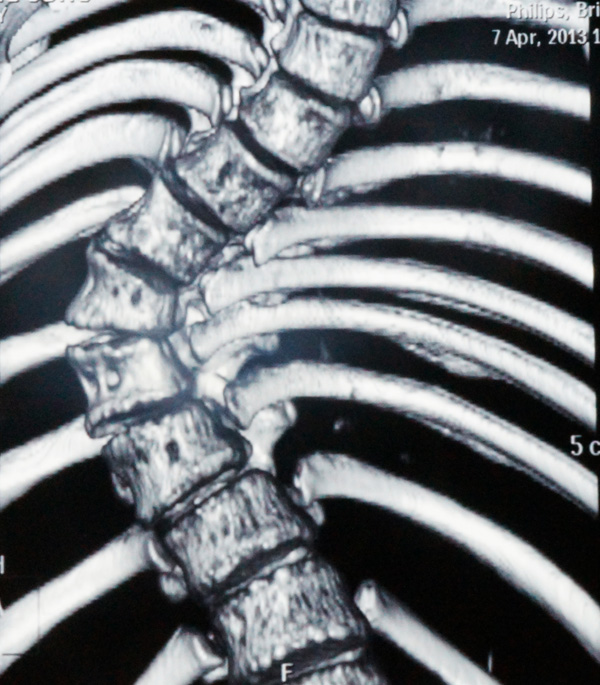

瑞康医院骨脊柱二区的医生给小松做了详细的身体检查,发现他的胸5-腰1椎体节段明显向右侧侧弯,呈小“S”形状,胸5-腰1棘突及棘突两旁无明显压痛及叩击痛,右侧竖脊肌肌张力紧张,左侧正常,站立姿势时测量左侧肩比右侧肩高约2cm。同时进行并足前屈弯腰试验时,发现小松的右侧肩胛骨明显高于左侧,出现“剃刀背”畸形,脊柱左右侧弯柔软性差,Cobb角65°[i],胸腰椎MRI平扫检查确诊:脊椎侧弯畸形。

小松术前的X光片2